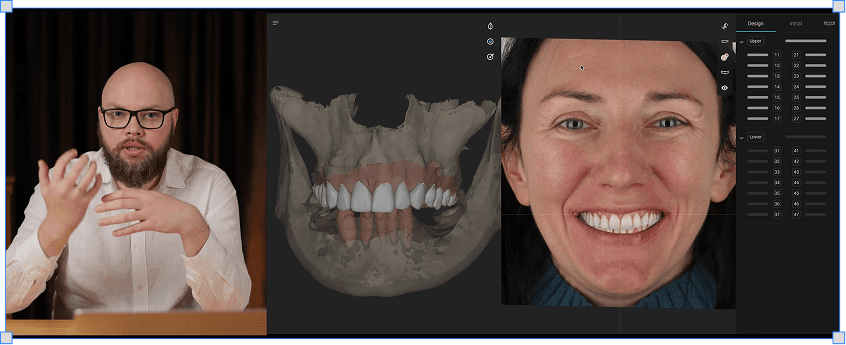

Кирило Антоненко

Секс і фото в стоматології

4 модулі

3 години

База про функціональну стоматологію: ЦО/ЦС/МССП

Функціональна діагностка: аналоговий і цифровий протоколи

Перенос даних в цифру і створення цифрового Wax-up